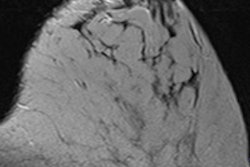

Dedicated breast CT doesn't require compression and it produces images that are not compromised by the tissue overlap inherent in mammography, O'Connell and colleagues wrote. Breast MR and automated whole-breast ultrasound also avoid tissue compression and offer 3D images, but dedicated breast CT provides higher spatial resolution than these other technologies.

Tomosynthesis acquires data that are reconstructed into slices to provide a "quasitomographic" view of the breast, the authors wrote. This is helpful, but the data are limited compared to 3D breast CT, in that the tomographic system's ability to separate the slices (its "slice sensitivity profile") worsens with larger breast diameters. Breast CT's slice sensitivity remains constant, and it generates images across any desired plane with consistent resolution.